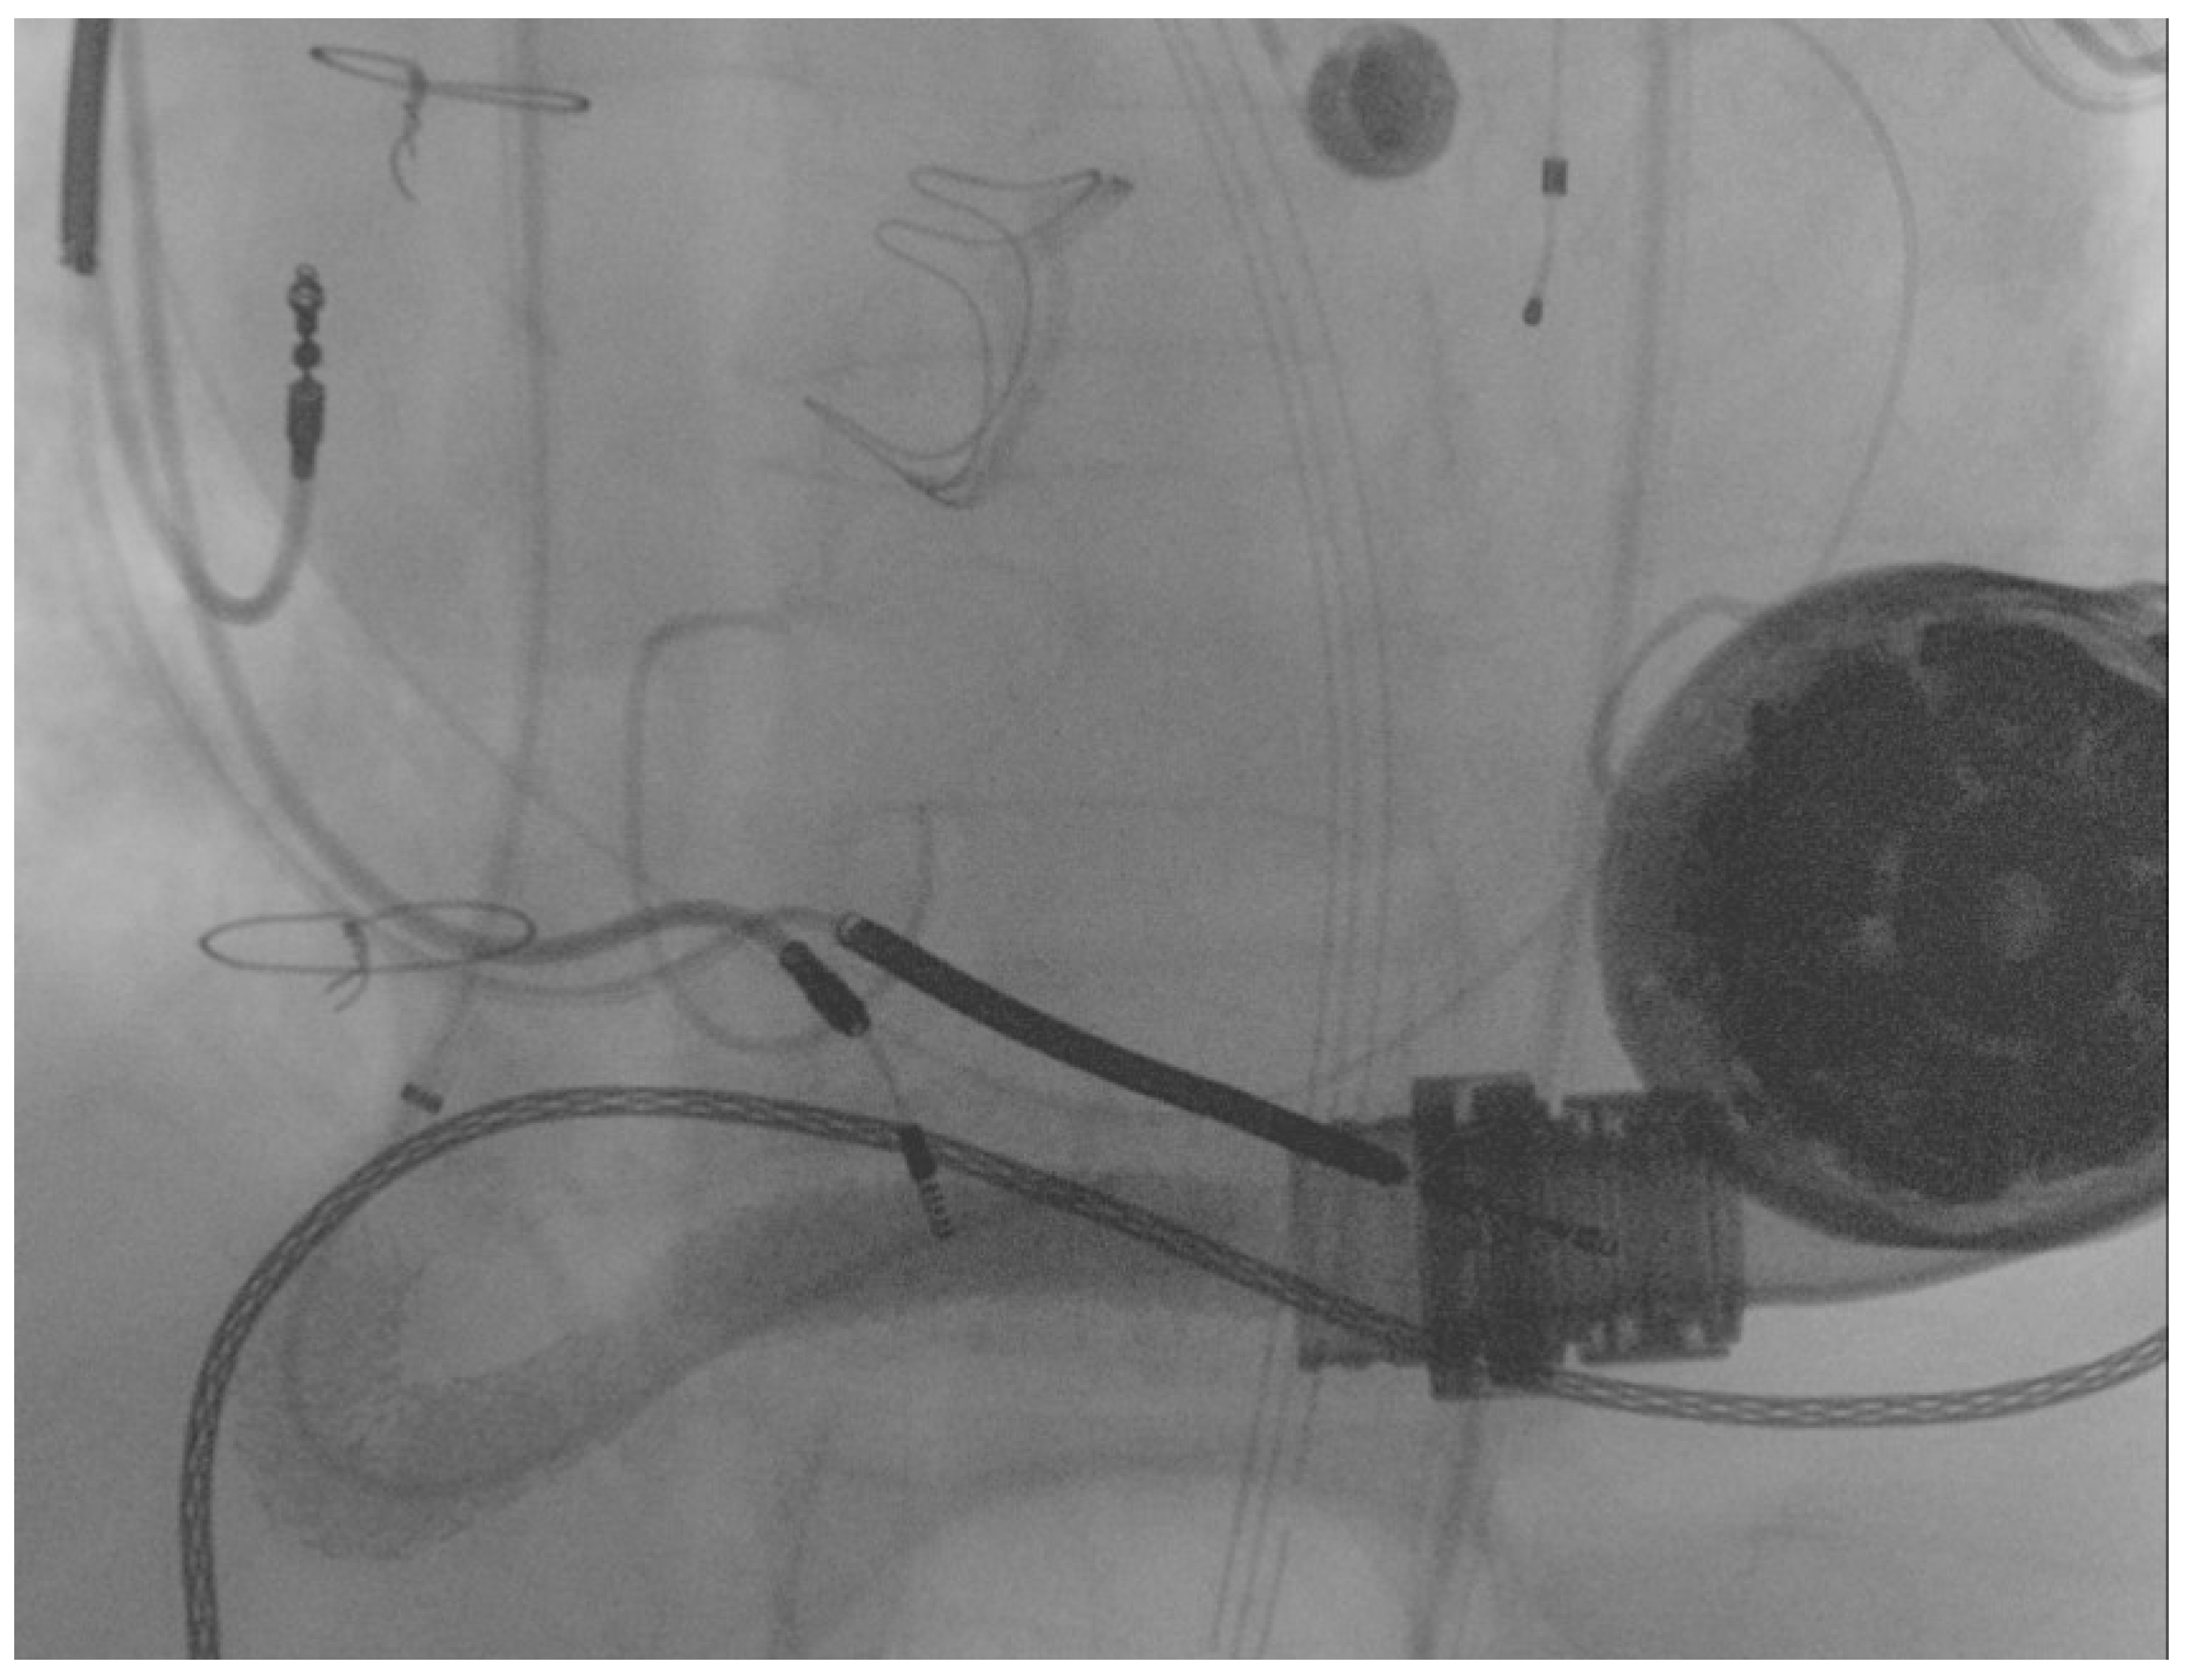

The first guidewire was removed and a 0.035″ × 260 cm stiff guidewire (Amplatz Super Stiff™, Boston Scientific, Natick, MA, USA) was deployed distally. Following this, an “anchoring technique” [8] with a 12 mm balloon located in the proximal tract of the outflow graft was adopted in order to advance the long sheet throughout the kinking. After that, a balloon-expandable 10 × 79 mm endoprosthesis (GORE® Viabahn® VBX) was implanted. Distal anchoring and stent positioning are shown in Figure 3A,B.

Figure 3.

(A) distal anchoring; (B) stent deployment.